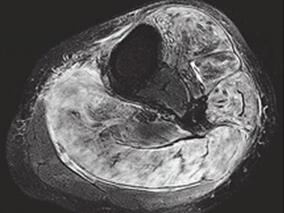

1小时条评论【病例资料】 患者,男性,37岁。因双侧马蹄足术后约26年,上楼及举物困难2年于2008年11月3日收入院。 现病史:患者26年前因双侧马蹄内翻足在积水潭医院行手术矫治,据患者回忆术前有足下垂、内翻,无明显运动障碍,术后生活学习不受影响,在校期间体育成绩属中等...